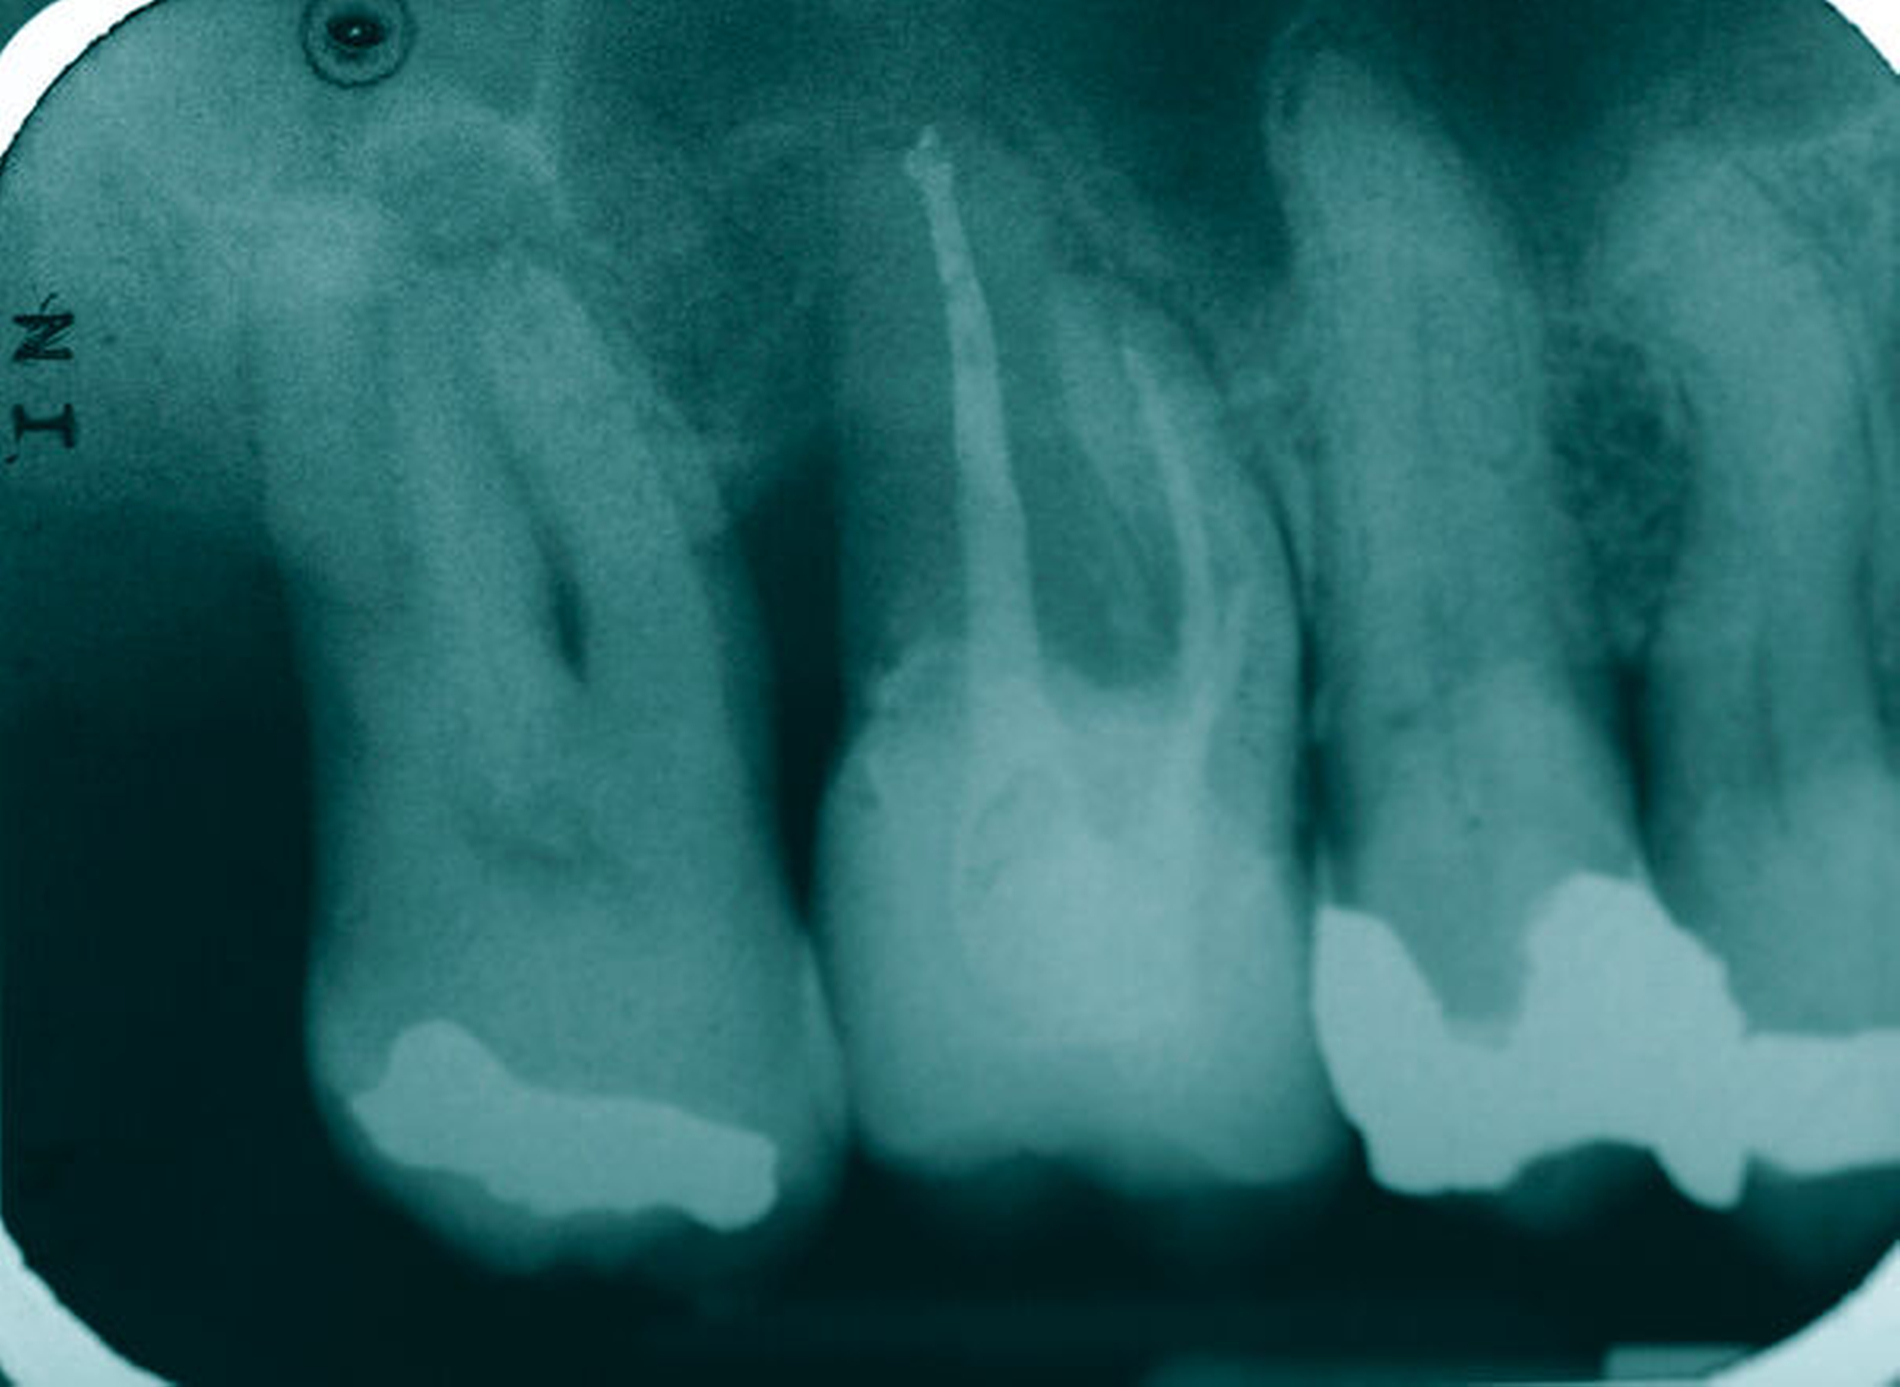

Tiefe Fraktur in mesiodistaler Richtung (Fall Nr. 6)

Eine 54-jährige Patientin stellte sich 2018 in der Praxis vor, nachdem sie beim Essen ein Goldinlay an Zahn 16 verloren hatte. Sie klagte über eine Aufbissempfindlichkeit des Zahnes sowie über das Gefühl einer Lockerung. Klinisch zeigte sich eine tiefe Fraktur des Zahnes in mesiodistaler Richtung. Nach klinischer und röntgenologischer Diagnostik wurde die Patientin über die Möglichkeit der Extraktion mit anschließender prothetischer Versorgung der Lücke und den aufwendigen Erhaltungsversuch mittels endodontischer Behandlung des Zahnes samt Amputation der palatinalen Wurzel aufgeklärt. Die Patientin war sehr motiviert und entschied sich für den Erhaltungsversuch.

So erfolgte nach endodontischer Behandlung des Zahnes die Amputation der palatinalen Wurzel und die Versorgung des Zahnes mit einer Vollkrone. Die Situation an 16 ist seitdem stabil, allerdings zeigen sich auch hier palatinal erhöhte Sondierungstiefen, die röntgenologisch mit einem progredienten Knochenabbau im Bereich der Furkation zu korrelieren scheinen. Die Patientin gibt an, mit der Reinigung des Zahnes keine Probleme zu haben, möglicherweise ist diese jedoch durch die Einziehung im Bereich der Furkation vor allem palatinal erschwert. Die Patientin wurde daraufhin instruiert, wie sie die häusliche Mundhygiene in den schwer zugänglichen Bereichen intensivieren und verbessern kann.